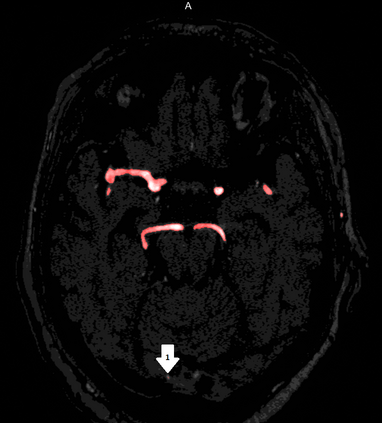

Deep learning approaches may help radiologists in the early diagnosis and timely treatment of cerebrovascular diseases. Accurate cerebral vessel segmentation of Time-of-Flight Magnetic Resonance Angiographs (TOF-MRAs) is an essential step in this process. This study investigates deep learning approaches for automatic, fast and accurate cerebrovascular segmentation for TOF-MRAs. The performance of several data augmentation and selection methods for training a 2D and 3D U-Net for vessel segmentation was investigated in five experiments: a) without augmentation, b) Gaussian blur, c) rotation and flipping, d) Gaussian blur, rotation and flipping and e) different input patch sizes. All experiments were performed by patch-training both a 2D and 3D U-Net and predicted on a test set of MRAs. Ground truth was manually defined using an interactive threshold and region growing method. The performance was evaluated using the Dice Similarity Coefficient (DSC), Modified Hausdorff Distance and Volumetric Similarity, between the predicted images and the interactively defined ground truth. The segmentation performance of all trained networks on the test set was found to be good, with DSC scores ranging from 0.72 to 0.83. Both the 2D and 3D U-Net had the best segmentation performance with Gaussian blur, rotation and flipping compared to other experiments without augmentation or only one of those augmentation techniques. Additionally, training on larger patches or slices gave optimal segmentation results. In conclusion, vessel segmentation can be optimally performed on TOF-MRAs using a trained 3D U-Net on larger patches, where data augmentation including Gaussian blur, rotation and flipping was performed on the training data.